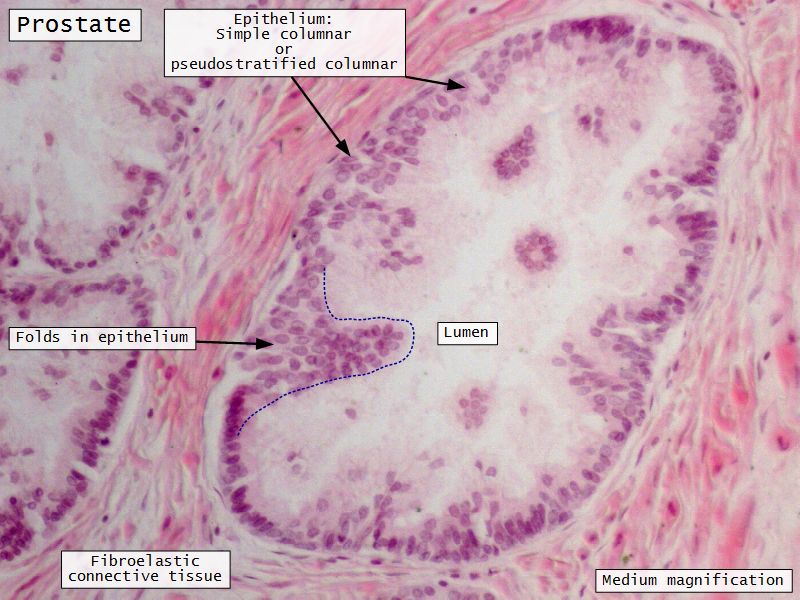

Prostate

Slide 80Prostate

Epithelium

- Simple columnar or

- Pseudostratified columnar

- Surrounded fibroelastic CT

- CT with rich vascular supply